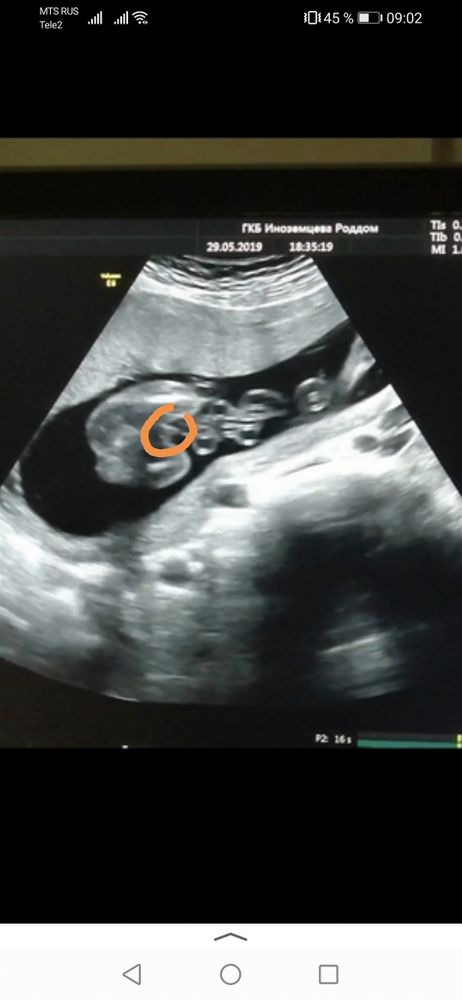

Я голосую за мальчика. На первом снимке мошонка и пипка. На втором снимке все плоско по ощущениям срез плоскости выше гениталий. На девочку не похоже потому что там все плоско, а у девочек не должно быть плоско, там типа персика должно быть или кофейного зерна. Т.е. как мошонка, но с серой полоской посередине.

Анастасия, это вид снизу, там 2 ножки и между ними причинное место, я бы скинул видео полное, но тут только фото можно 🥲

Хех, я вижу девочку на обоих фото. Переделайте у другого специалиста в другой клинике для уверенности. Вот мой мальчик в 19 недель. Очевидно же. Изображение

Лиза Бушкевич, ну, у меня причинное место обведено: хорошо видно пенис, мошонку не очень. Это стоп-кадр с видео.

Я на втором вижу девочку🙈

Enot v teme , В этом то и подвох😂 Что на первом вроде мальчик а на 2 девочка😄